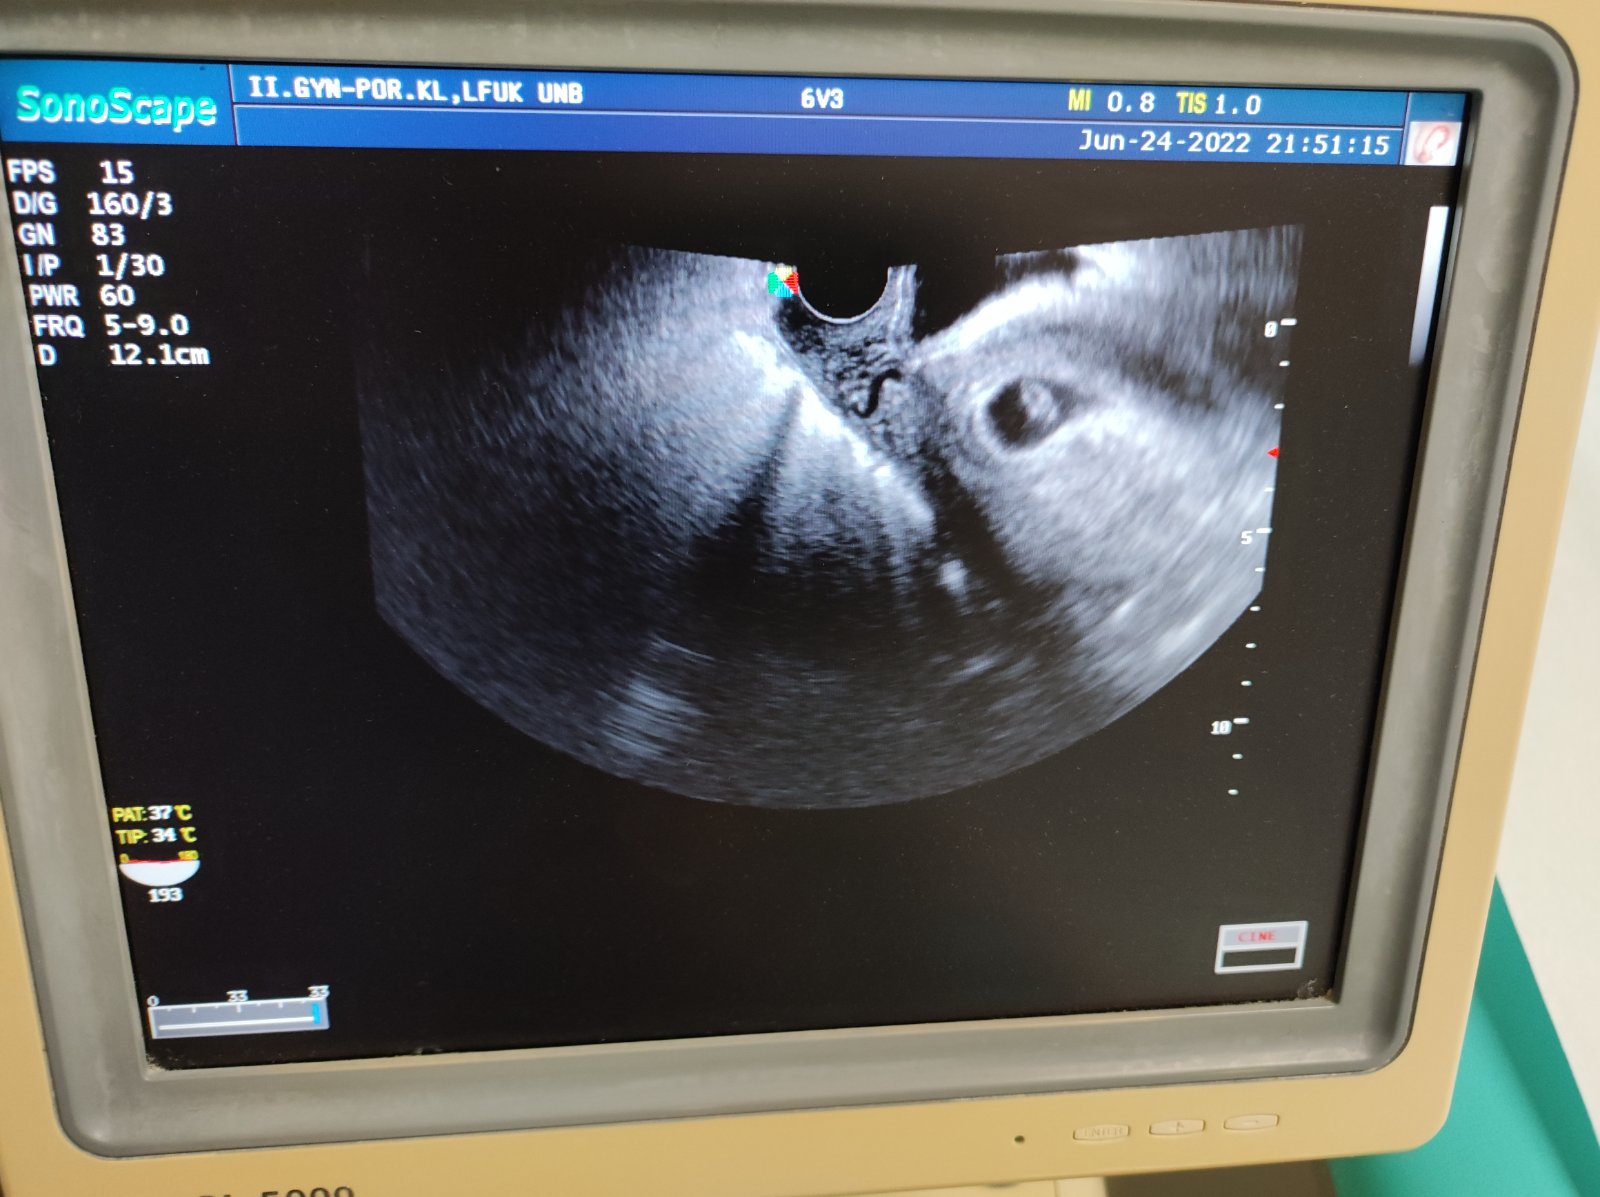

Sla som na wc a bum krv jasna cervena pri utreti. Tak som hned sla na pohotovost. Zlakla som sa a teda kedze mame ist to oznamit rodine chcela som vediet co sa deje. Nastastie ako tehotnu ma vysetrili okamzite.naozaj na prekvapenie som necakala ani minutu.lekar sice ma zdžubal ze som prisla hned pri nejakom slabuckom krvacani, ze mam vlozku cistu cistu,ze on by svoju zenu na pohotovost neposlal.ze keby vysetroval kazdu ktora zakrvaca tak by nerobil nic ine. No ale ja som nazoru ze radsej 100x zbytocne ako nieco zanedbat. Pri vysetreni videl kde to zakrvacalo niekde v krcku, ze vyzera byt vsetko ok. Dal mi pocut srdiecko, vyrastli sme o milimeter od stvrtku. Predpisal mi utrogestan.tak dufam,ze uz nebudem ani spinit ani nic...